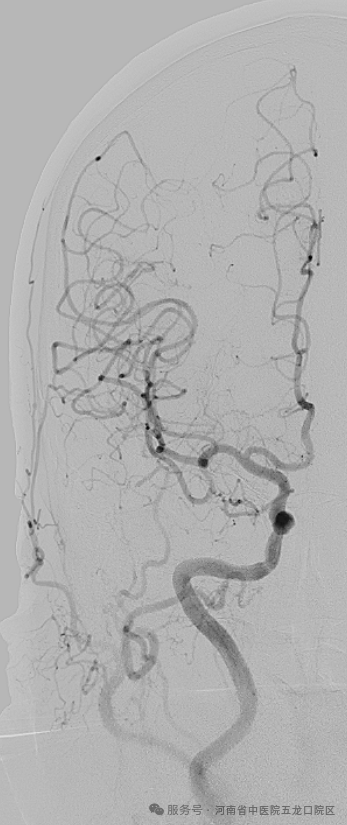

此次首例脑血管造影的顺利开展,正是科室同质化建设的重要成果。术前,程率芳主任带领团队完善术前讨论、制定周密方案;术中,姬令山副主任现场指导,团队配合默契,精准完成操作,整个过程顺利流畅,为患者后续诊疗提供了清晰可靠的诊断依据。同时,科室还响应“泛血管病”诊疗理念,联合心病科完成了脑血管-冠脉联合造影,实现了心脑血管疾病的同步评估,为合并心脑血管共病的患者提供了一站式诊疗服务。

此次首例脑血管造影的开展,只是五龙口院区脑病科规范化诊疗的一个缩影。科室依托院本部成熟的神经介入团队和卒中诊疗体系,常态化开展脑血管造影术、介入取栓术、血管内支架成形术、脑动脉瘤栓塞术等多项前沿技术,同时搭建了7×24小时卒中绿色通道,脑病科专科医师全天候值班,卒中急救电话15378761120随时畅通,为急性脑梗死、脑出血、蛛网膜下腔出血等危急重症患者争分夺秒开展积极有效的规范化救治,为守护人民群众的脑健康保驾护航!(文/郑伟锋 徐晓玉)